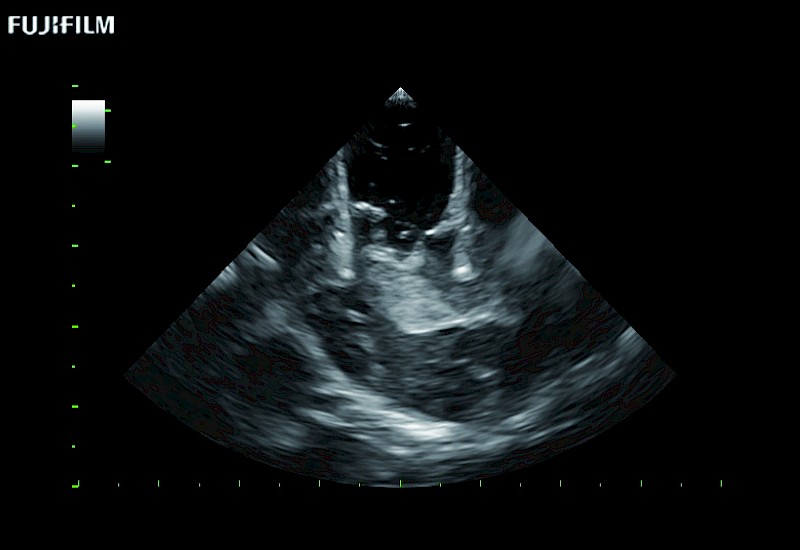

Smaller footprint (20mm) curved array transducer that is ideal for scanning during cranial guidance procedures.

Main Specifications: